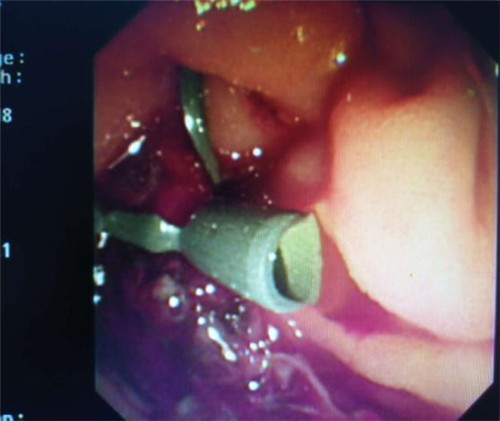

经过多个科室的配合,在介入科X线机下,曹鹏医生于十二指肠镜下顺利将导丝插入患者胆管内,注入二氧化碳气体造影,X线下见患者肝内外胆管扩张,胆管末端明显有占位性病变,患者胆管末端因肿瘤压迫,非常狭窄,经过多级扩张后,顺利为患者置入胆道支架。手术非常顺利,患者生命体征平稳,大家都松了口气。